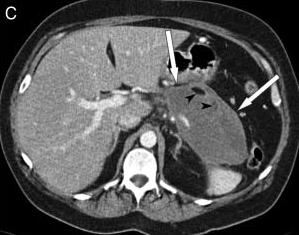

Nekrotizanpankreatit her zaman olmasa da genellikle ödematöz pankreatitten daha ağır klinik seyir gösterir. Nekrotizan-ödematöz ayrımını yaptıran yöntem kontrast maddeli bilgisayarlı tomografidir. Nekrotizan pankreatit üzerine enfeksiyon eklendiğinde ‘enfekte pankreas nekrozu’ olarak adlandırılır. Ağır bir klinik tablo olan bu durumda genel olarak nekroz cerrahi veya daha az sıklıkta da radyolojik olarak boşaltılamazsa ölüm oranı çok yüksektir. Nekrotizan ve enfekte nekrotizan pankreatitlerin tedavisi bu konuda deneyimli yoğum bakım uzmanlarının, radyologların ve cerrahların bulunduğu bir ortamda tedavi edilmelidir.

Akut pankreatitin seyri sırasında pankreas etrafında sıvı birikimi sık görülür. Bu toplantıların etrafında belirgin duvar yapısı yoksa ‘akut sıvı koleksiyonu’ olarak adlandırılır. Bunlar genellikle izlem sırasından herhangi bir işlem gerekmeden kaybolurlar. Eğer bu sıvı birikimlerinin etrafında belirgin duvar yapısı varsa ‘pseudokist’ olarak adlandırılırlar. Pseudokistlerin bir kısmı zaman içerisinde kendiliğinden iyileşebilir. Ancak boyutu 6 cm’den büyük olanlarda bu durum daha az görülür. Pseudokistler eğer herhangi bir probleme neden olmuyorlarsa uzun süre izlenebilirler. Komşu organlara bası belirtileri varsa, iltihaplanırlarsa veya içlerine kanama olursa girişim gerektirirler. Dışarıdan dren konulması, endoskopik işlemler veya cerrahi tedavi seçeneklerinin tercihi kistin konumuna, komplikasyonun ne olduğuna, hastanın genel durumuna göre değişkenlik gösterir. Hangi tedavinin uygun olduğuna hastayı takip eden cerrah-gastroenterolog-radyolog ortaklaşa karar verir.